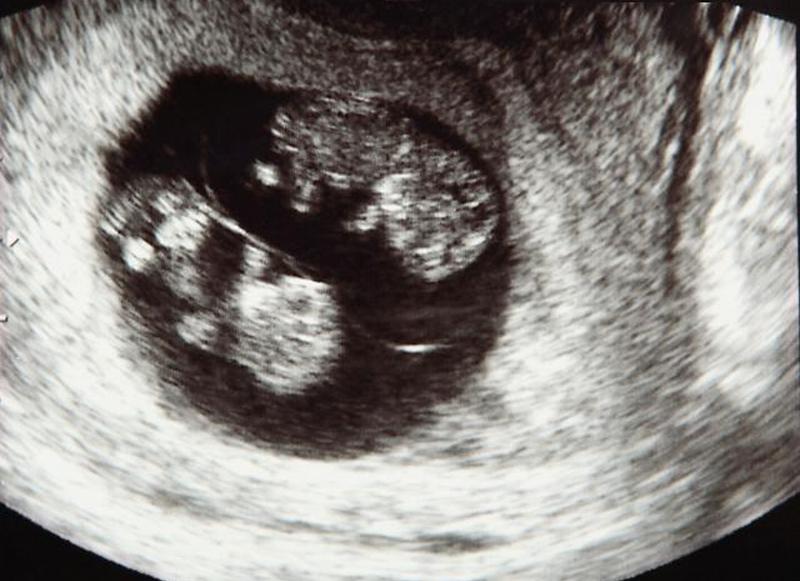

- Для Почему УЗИ для беременных так важно , чтобы проверить на здоровье младенцев, плацентарной функции, на фундальной высоте матки и количестве амниотической жидкости